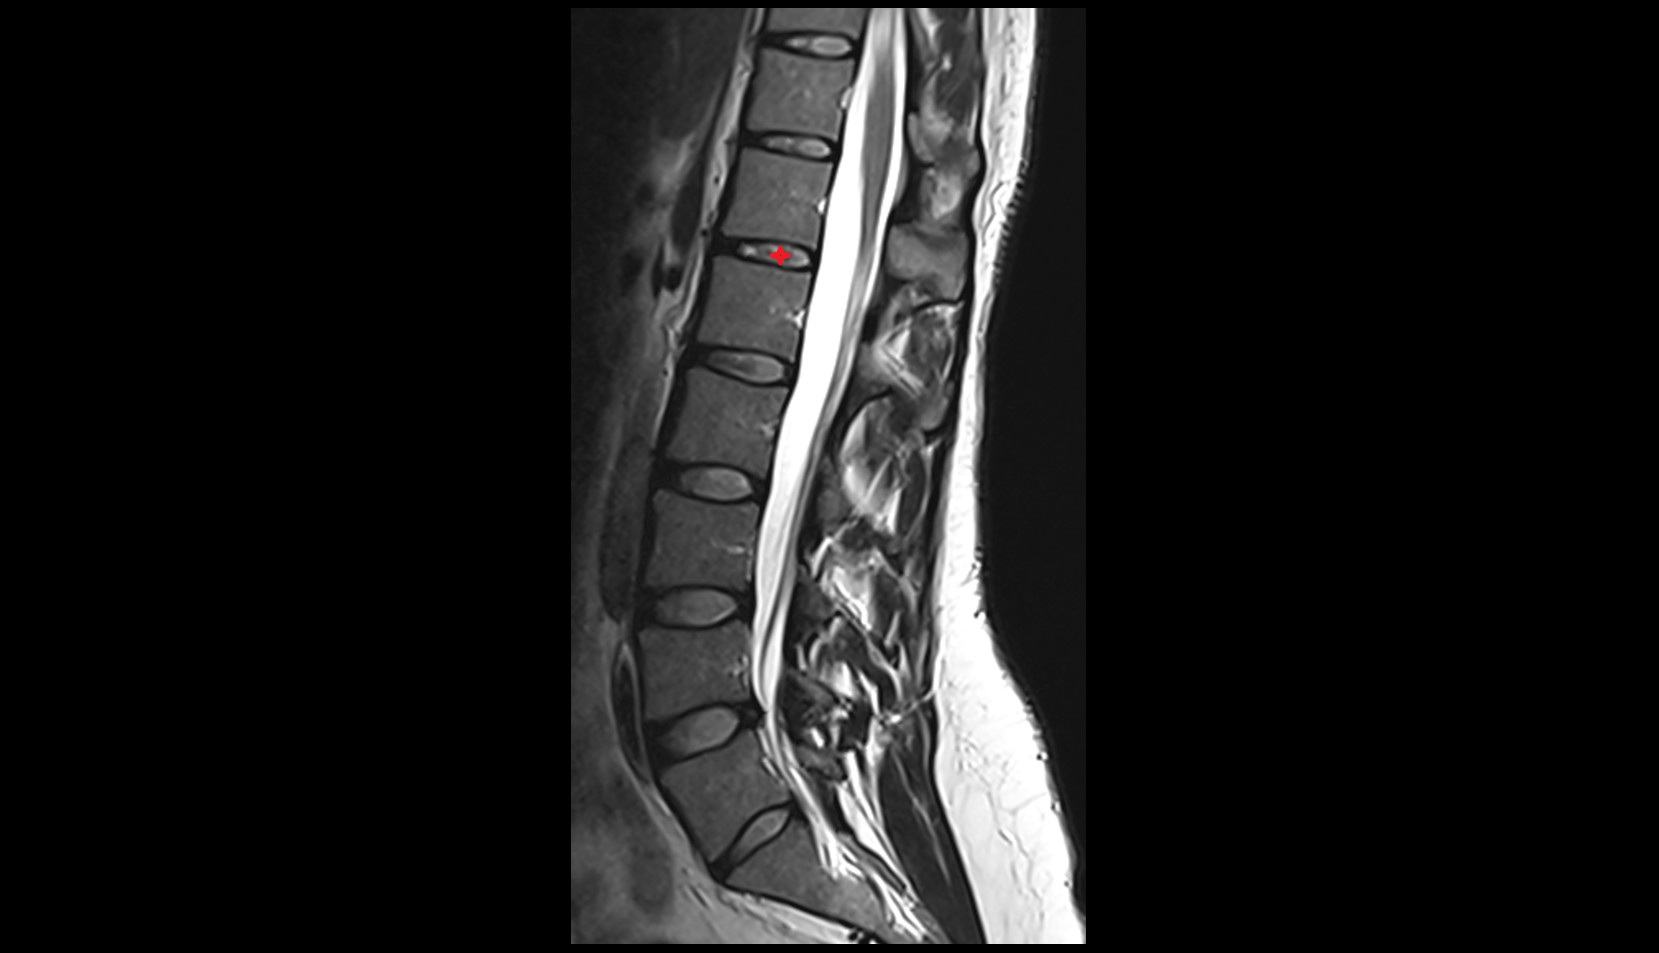

MRI image

T12-L1  Intervertebral Disc mri anatomy  image